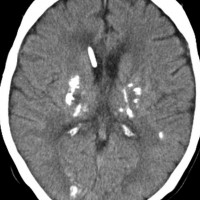

全脳照射後の脳内石灰化(青年期例)

1985年,17才のときに松果体ジャーミノーマで全脳照射45グレイ,18分割,1回2.5グレイの放射線治療を受けました。照射後の数年は普通に社会復帰ができていたということで,大学を卒業し,就職もしていました。しかし,20代後半くらいから認知機能低下(高次脳機能障害)が目立つようになりました。41才で脳幹部梗塞になりましたが,放射線治療が原因の脳血管障害でした。大脳にも小脳にも広範囲に脳内石灰化が散らばっています(白い点状に見えるもの全て)。30代からさらに進行悪化しました。脳の萎縮は目立ちませんが,MRIでは,大脳基底核の多数のラクナ梗塞,多数の海綿状血管腫,中大脳動脈の壁不整と狭窄もみられました。45才で介護施設に入所しています。このような所見は,1日線量2.5グレイを用いていた頃の小児患者さんでみられます。